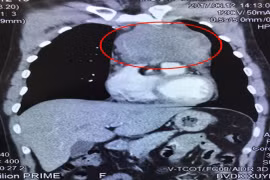

Ngày 21-8, Bệnh viện K Trung ương cho biết, các bác sĩ của bệnh viện vừa phẫu thuật cắt thành công khối u khổng lồ ở tủy sống và lồng ngực rất hiếm gặp cho một nữ bệnh nhân 61 tuổi ở Quảng Ninh.